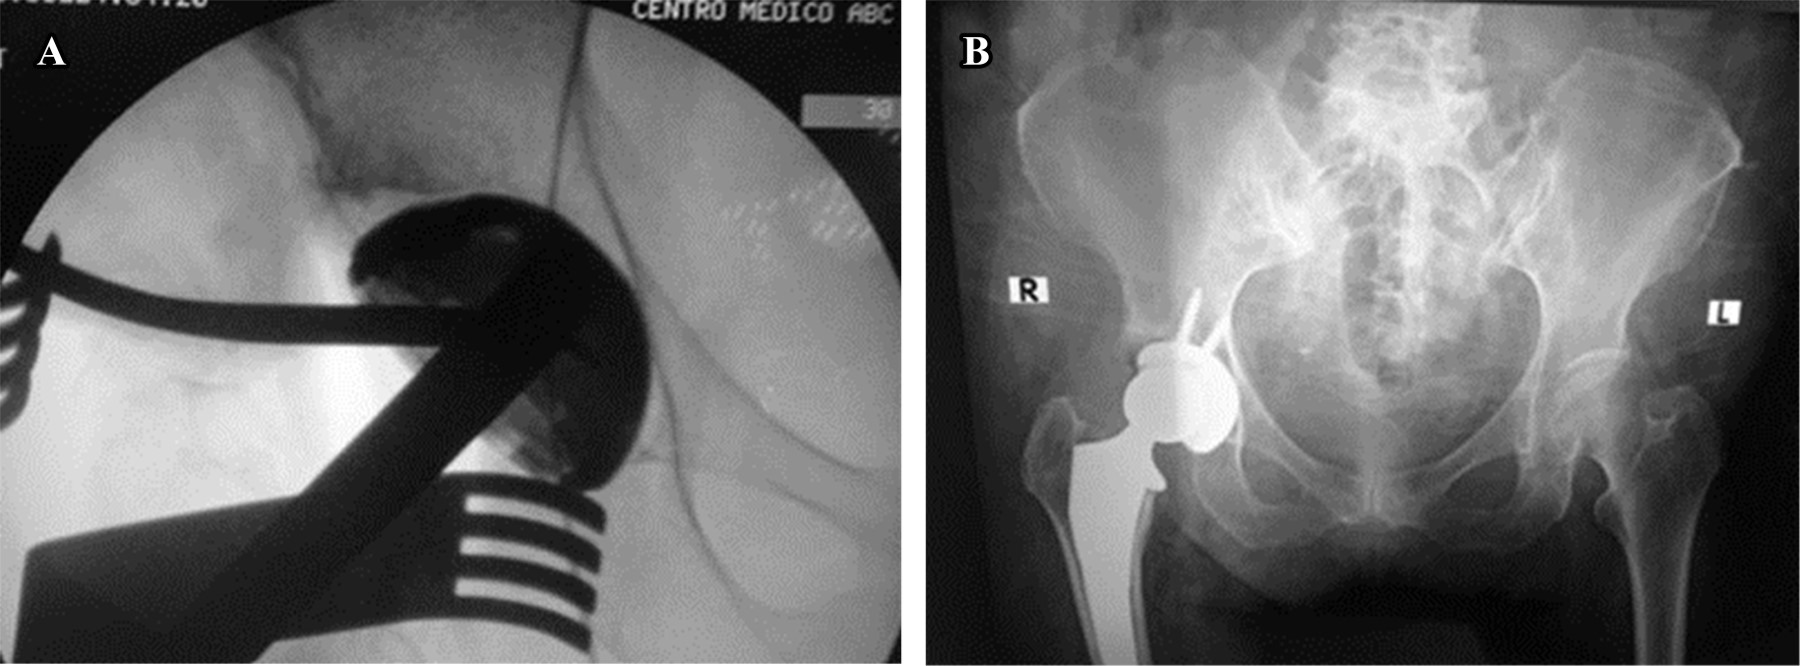

A more severe complication is the broaching-related perforation of the femoral cortex as a result of improper broach location (Figure 4).

One must be aware of the femur's situation because a posterior perforation translates into a perforation of the lateral femoral cortex (extreme varus) when the femur is 90° or more externally rotated during preparation. Superior soft tissues can occasionally direct the broach in this direction.

The traction table enhances this exposure by hyperextension of the hip. When the traction table is not used, it is essential to perform appropriate soft tissue releases around the femur osteotomy to obtain a good view of the femoral canal. The releases usually include piriformis and a partial detachment of the posterior capsule. Intraoperative imaging should be done when any concern exists to ensure proper implant or broach position. Short, curved stems are preferred over standard straight ones; thus, less stress is transmitted to the greater trochanter, thus dismissing fracture risk.

INTRAOPERATIVE FRACTURES

Intraoperative femoral or acetabulum fractures must be addressed. Femoral fractures could occur as with any other surgical approach for THA during stem insertion, and these injuries can be divided into two types: calcar or greater trochanter fractures. For the anterior approach, the reported rate ranges between 1.0 and 2.2% in multiple papers, with a little over half requiring fixation. Calcar fractures should be treated with cerclage and greater trochanter fractures with observation19,20 (Figure 5).